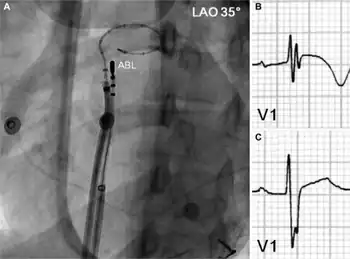

Catheter ablation involves advancing several flexible catheters into the patient's blood vessels, usually either in the femoral vein, internal jugular vein, or subclavian vein. The catheters are then advanced towards the heart. Electrical impulses are then used to induce the arrhythmia and local heating or freezing is used to ablate (destroy) the abnormal tissue that is causing it. Originally, a DC impulse was used to create lesions in the intra-cardiac conduction system.[6] However, due to a high incidence of complications, widespread use was never achieved. Newer procedures allow for the terminating of diseased or dying tissue to reduce the chance of arrhythmia.

One type of catheter ablation is pulmonary vein isolation, where the ablation is done in the left atrium in the area where the 4 pulmonary veins connect.[7][8]

Catheter ablation is usually performed by an electrophysiologist (a specially trained cardiologist) in a cath lab or a specialized EP lab.